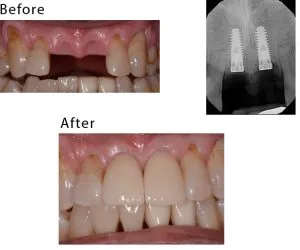

case-studies Case #3 This patient lost his teeth because of periodontal disease. They were restored with implant-supported crowns.February 26, 2024/by Rich https://sunnyvaledentalspecialty.com/wp-content/uploads/2018/08/blog2.jpg 512 614 Rich https://sunnyvaledentalspecialty.com/wp-content/uploads/2017/03/logo.png Rich2024-02-26 12:31:502024-05-02 11:09:46Case #3